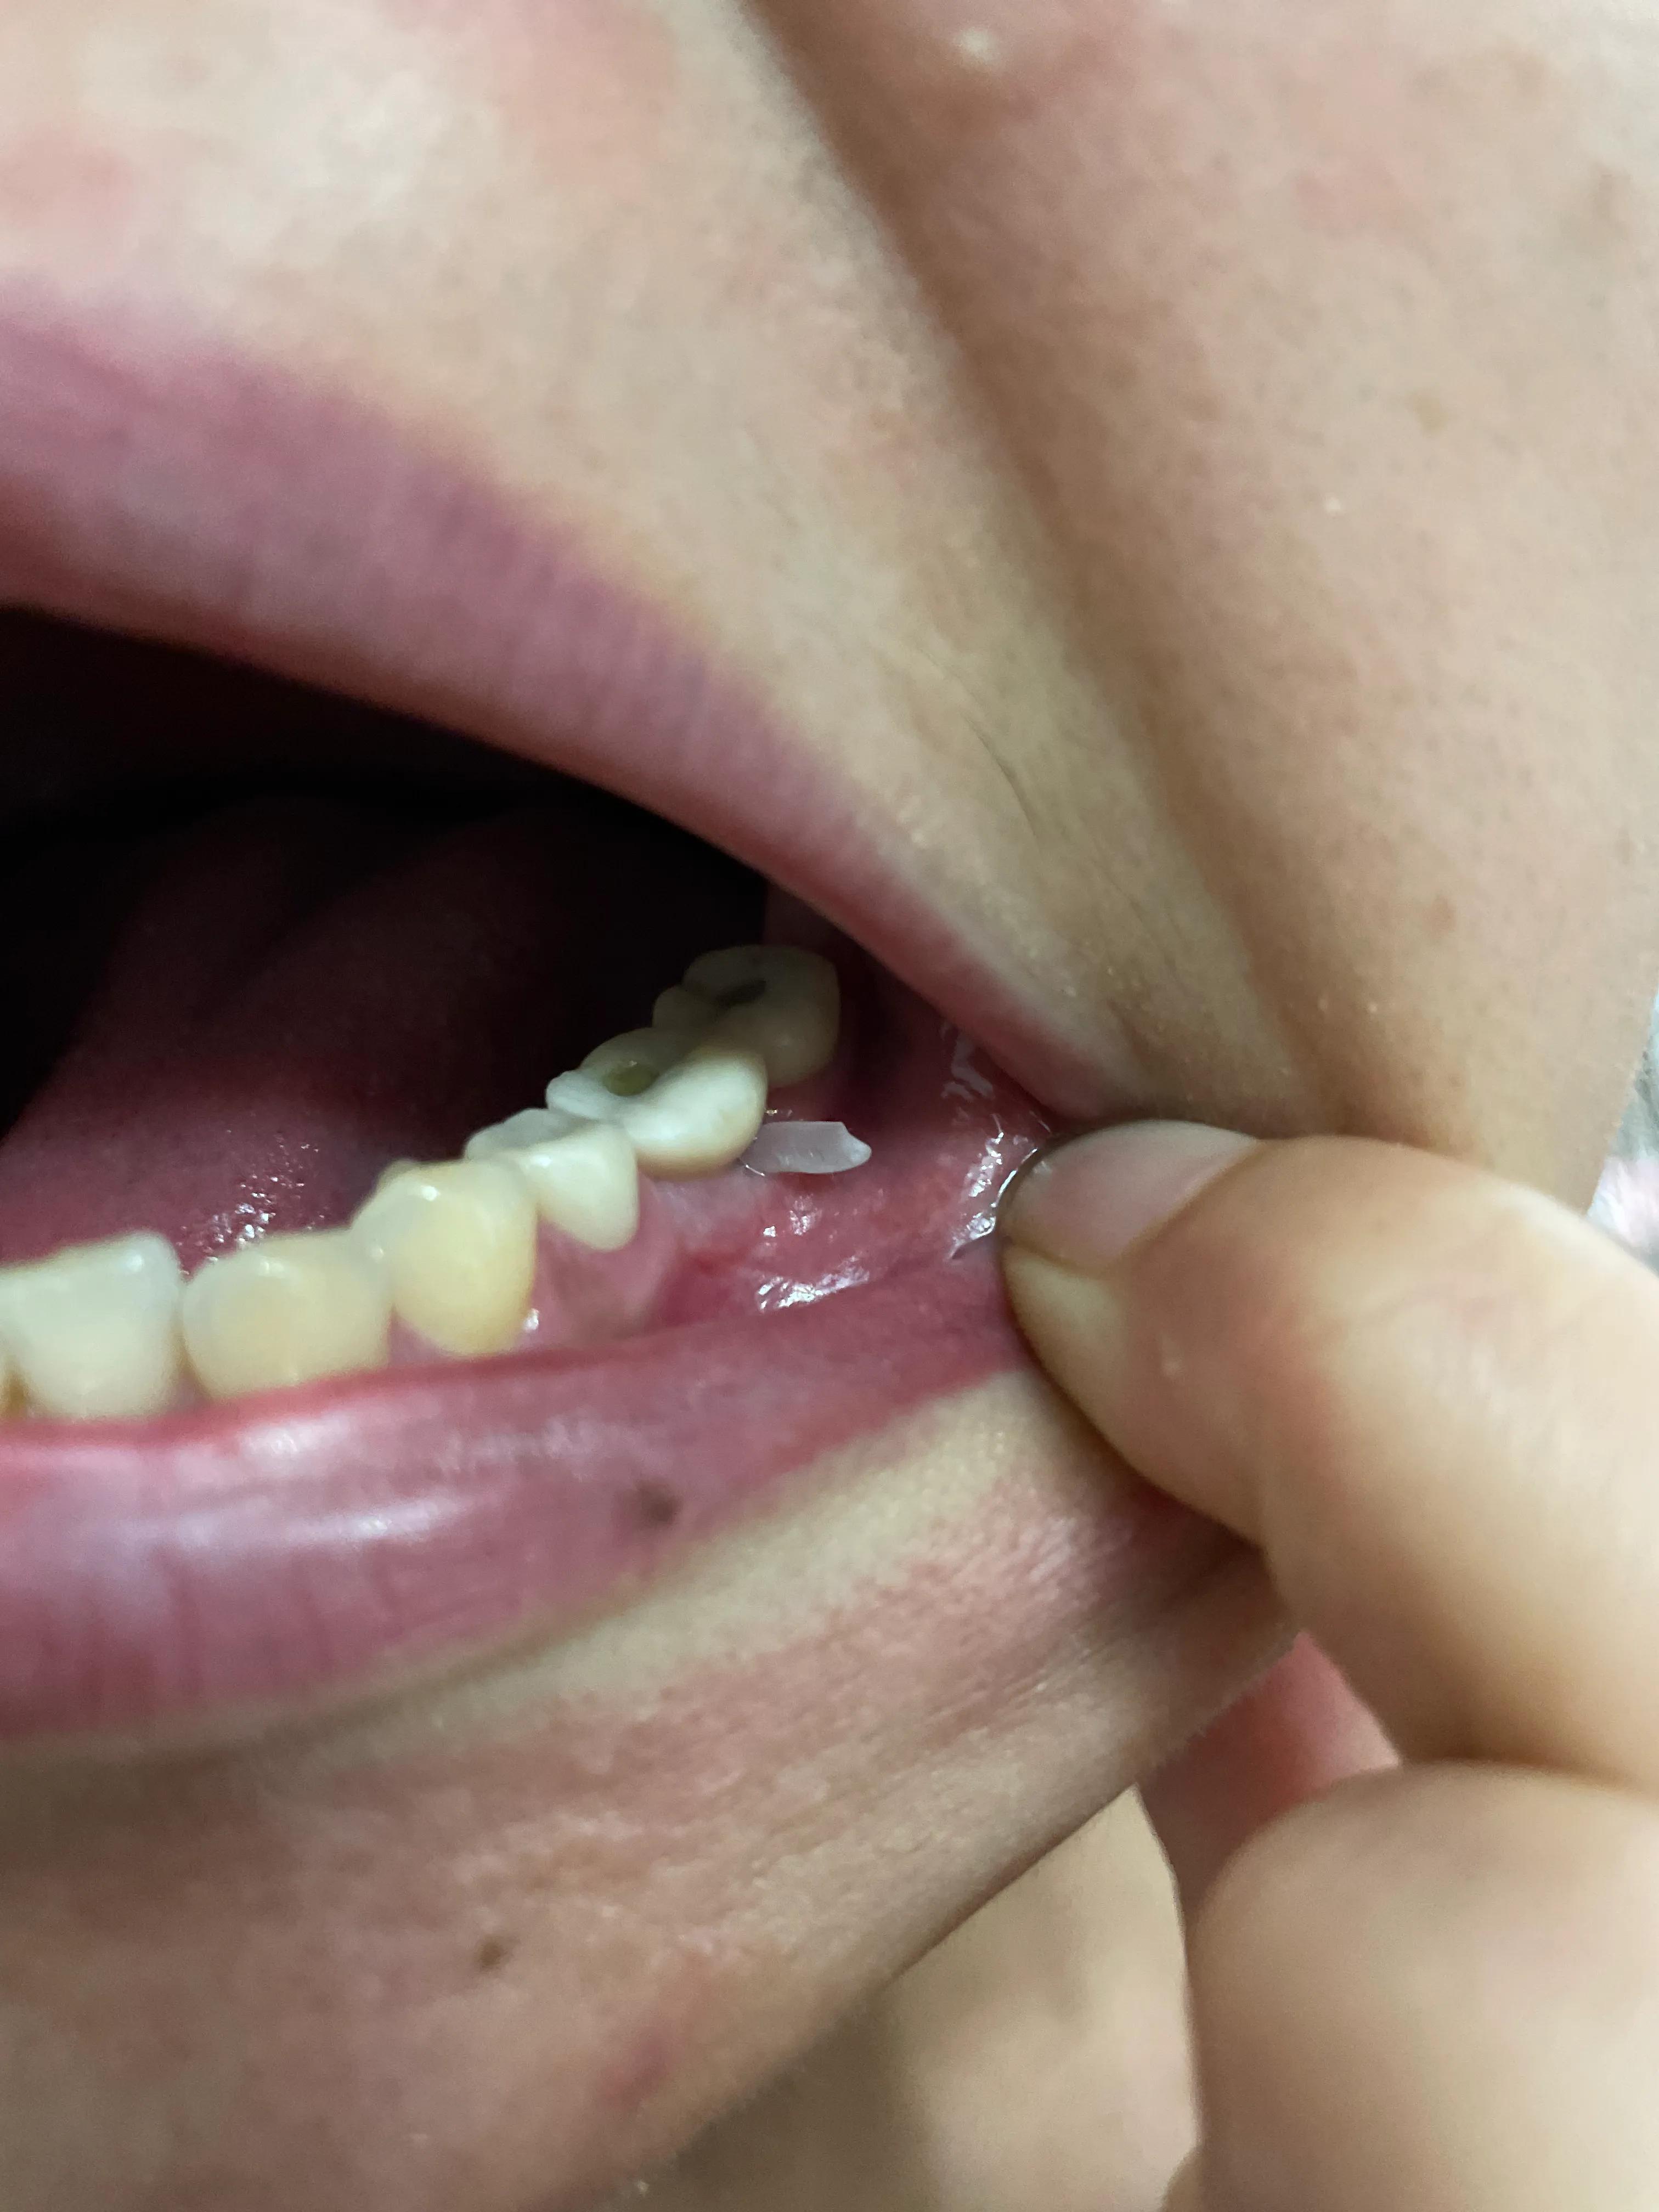

第二副牙帶好 發(fā)現(xiàn)牙齦又缺肉了 更別提貼合牙齒了 而且是一直的疼 一直難受

牙齦是外翻和牙齒分開(kāi)的 顏色發(fā)白 和其他部位牙齦不是一樣顏色

我不是專(zhuān)業(yè)醫(yī)生 不懂他們所說(shuō)的正常現(xiàn)象都包括什么 要怎么后期維護(hù) 我現(xiàn)在先不講看不見(jiàn)的難受 疼 先講直觀能看見(jiàn)的 他們哪位醫(yī)生可以做到把大米粒塞到牙齒下面 和將近半厘米的塑料條塞過(guò)他們的牙齒 吃過(guò)東西就要用沖牙器 不然隔頓就臭了

沒(méi)辦法自己又出去拍片子 找原因 看了幾家醫(yī)院 才知道連種植體也種偏了 牙冠也沒(méi)有就位………